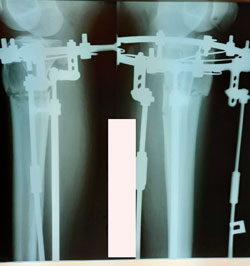

на фиксации

Вложения

image-09-12-20-01-53.jpg

image-09-12-20-01-53-1.jpg